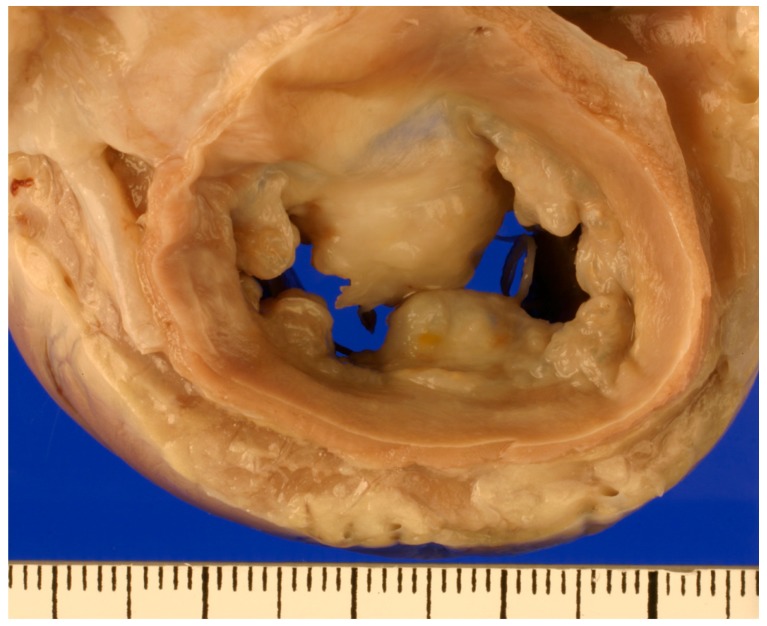

The pathophysiology involves progressive myxomatous degeneration characterized by: expansion of extracellular matrix with glycosaminoglycans; valvular interstitial cell transformation to myofibroblast phenotype; attenuation of the collagen-laden fibrosa layer; and chordae tendineae changes with potential rupture.

Figure 2 - Gross pathology of myxomatous mitral valve showing thickened, nodular valve leaflets

Reference: Menciotti G, Borgarelli M. Review of Diagnostic and Therapeutic Approach to Canine Myxomatous Mitral Valve Disease. Vet Sci. 2017 Sep 26;4(4):47. doi: 10.3390/vetsci4040047. PMID: 29056705; PMCID: PMC5753627.